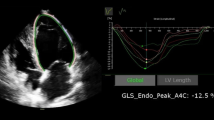

Pulse-wave doppler and tissue doppler echocardiography

In the apical four chamber view, doppler echocardiography was used to assess peak early diastolic transmitral velocity (E), peak late diastolic transmitral velocity (A), E/A ratio, and mitral E-wave deceleration time (DT). Tissue doppler velocity analysis was done by placing a 2 mm doppler sample in septal and lateral mitral annulus to measure septal and lateral peak early diastolic velocity (e’). E/e’ was calculated as E divided by the mean of septal e’ and lateral e’ (Fig. 1) [12]. Right ventricular systolic pressure was estimated using the tricuspid regurgitation jet velocity.

Doppler and strain echocardiographic images. Top left, pulsed-wave doppler recording at mitral inflow showing E, A velocities and E-wave DT. Top right, tissue doppler imaging at lateral mitral annulus showing e’. Mid left, region of interest tracing in the apical 4-chamber view during offline analysis using semi-automatic speckle-tracking software. Mid right, segments of left ventricle as seen in the apical 4-chamber view. Bottom left, peak systolic strain waveform obtained from apical 4-chamber view shown in mid panel. Bottom right, Bull's eye plot of longitudinal strain 3 apical views showing strain values of each segment

Speckle tracking echocardiography

Strain and strain rate analysis was done offline using GE EchoPac software v201 (EchoPAC Advanced Analysis Technologies; GE Healthcare, US). All measurements were performed as recommended by the 2010 EACVI/ASE/Industry Task Force consensus document [13]. Two-dimensional speckle-tracking was performed using the three standard apical views by first manually tracing the endocardium at the onset of systole after which the acoustic tracking software tracked the myocardial speckle pattern frame-by-frame throughout the cardiac cycle. The region of interest was adjusted to cover the thickness of the myocardium and adequate tracking was verified and corrected if necessary. The aortic valve closure was identified on continuous wave doppler recording through the aortic valve. The LV was subsequently divided by the software into 18 segments covering the entire myocardium. Longitudinal strain was calculated for each of these segments and global longitudinal strain (GLS) was calculated as the average value of all 18 segments (Fig. 1). Similarly, global systolic strain rate (SRS) and global early diastolic SR (SRE) and late diastolic strain rate (SRA) were calculated from the average of all 18 segments. The E/SRE ratio was calculated as the E velocity (m/s) divided by the global SRE value.